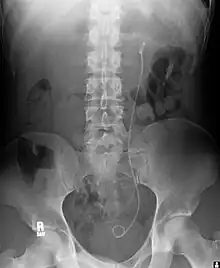

Radiographie révélant la présence d’une sonde double J

- (Médecine) Sonde urinaire passant par l’urètre, dont les extrémités en boucle sont placées dans un rein et dans la vessie, et occupant ainsi un uretère.